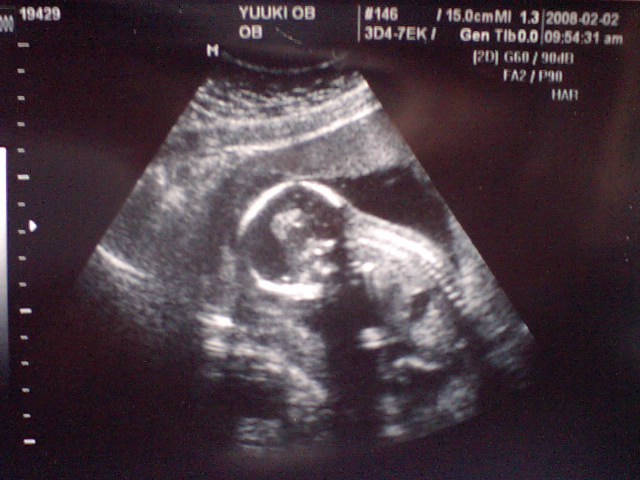

4週間ぶりの検診です

前回はたくさん検査(エイズ検査やらB型肝炎やら性病やら)を受けていて

その後の産院だったんで、検査結果が ドキドキ

・・・ではありましたが・・・

検査結果は異常なし!!!!

とのこと。

よかったぁあーーーー

そして今回のエコー写真 ↓

← わかりますかぁあ?

頭に体(背骨がくっきり!)に手足。

だいぶ発達したなぁと前回の写真から思います!

実は、ちょっと早いけど 性別もわからないかなぁ?

なんて淡い期待も抱きながら行ったのですが、

今回赤ちゃんは寝ていたようで(しかも立って寝ているからとのことで)

あまりあちこちの方向から見ることができませんでした・・・

くすん

(ちょっとだけ残念)